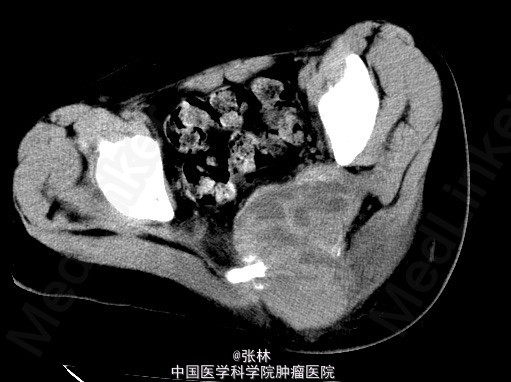

【临床病史】:患者,男,17岁,骶尾部肿物3个月,骶尾部及左腿疼痛20天,4个月前骶尾部有外伤史。【影像表现】:骶骨溶骨性骨质破坏,并软组织肿块。 【影像诊断】:神经源肿瘤? 脊索瘤?骨髓瘤? 【最后诊断】:术后病理结果:动脉瘤样骨囊肿。 【讨论】:动脉瘤样骨囊肿(ABC)为一充满血液的肿瘤样病变,因其外形似动脉瘤样的囊状膨出而得名。好发长骨干骺端和脊椎,年龄10-20岁。病因不明,一般以为外伤是重要诱因,外伤、静脉血栓、动静脉瘘、血管瘤、骨膜下囊肿或其他疾病因素导致局部血液动力的障碍、静脉压持续升高,患骨血管床扩张,压迫骨质吸收并寄发感染反应性修复而形成囊肿。特征性影像表现液-液平面;而脊索瘤应该有散在钙化;动脉瘤样骨囊肿的吸收性骨质破坏是此病例鉴别诊断的关键!